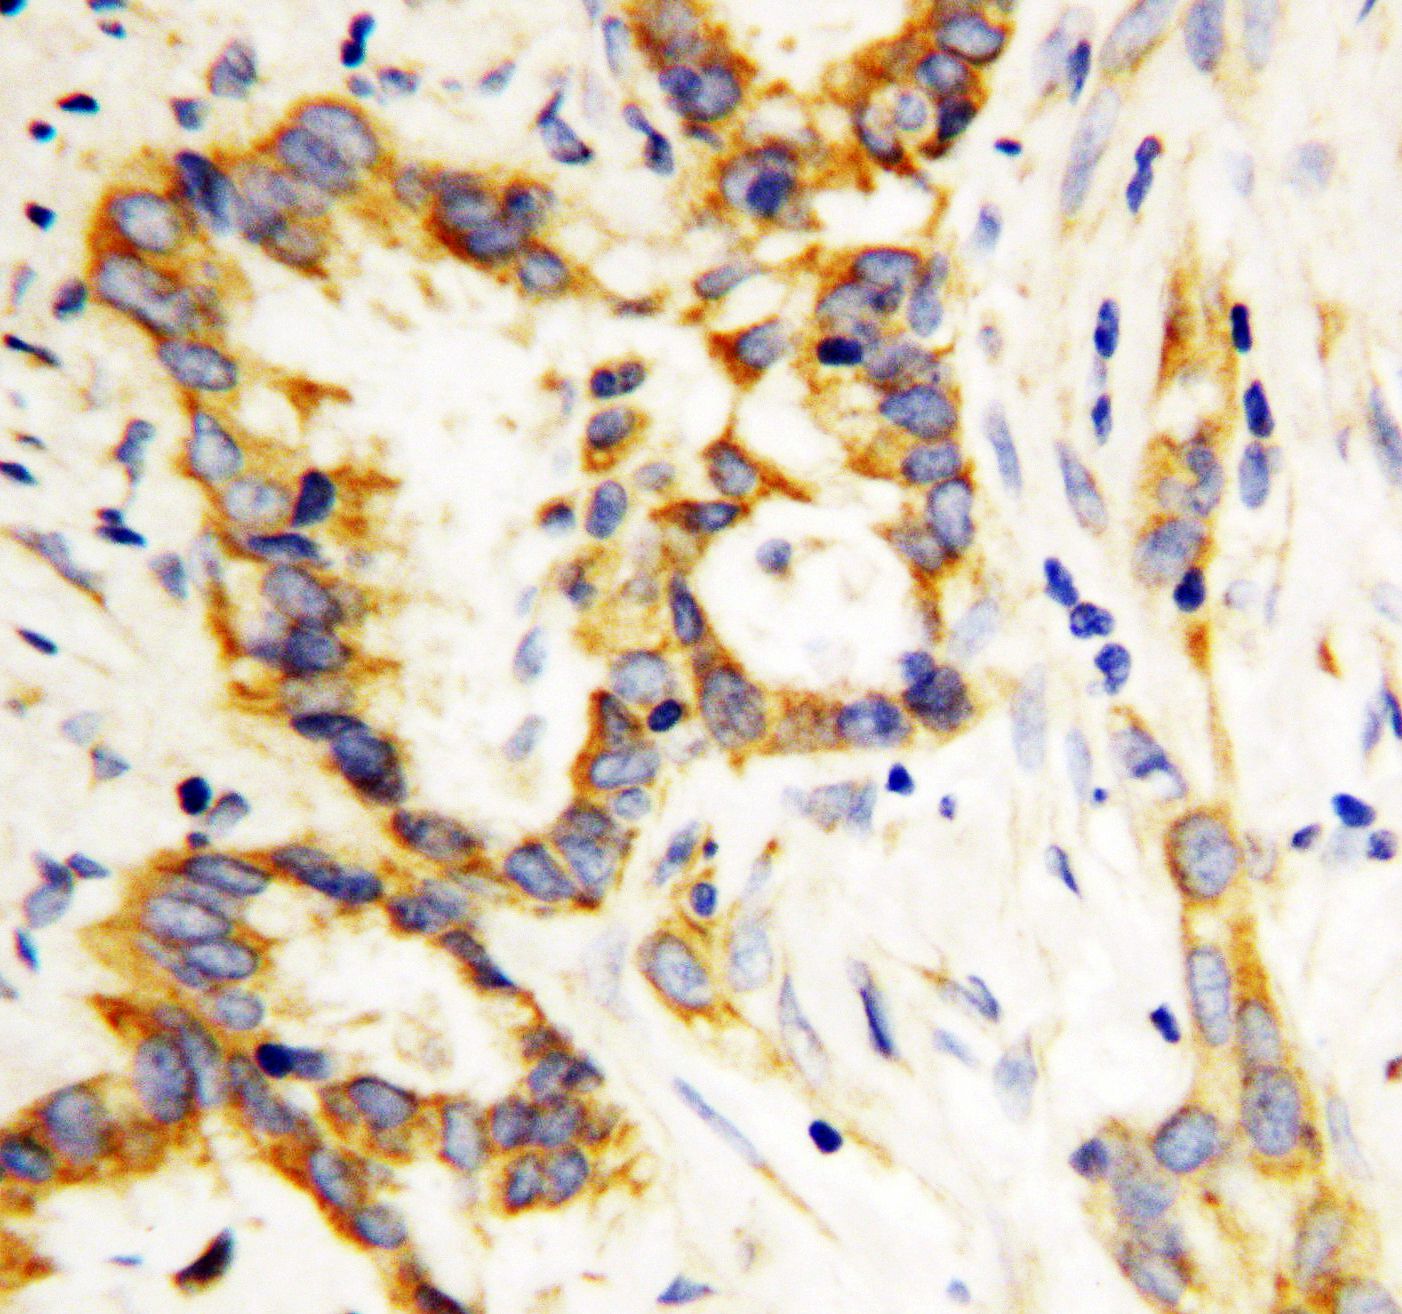

IHC analysis of Livin/BIRC7 using anti-Livin/BIRC7 antibody (BA1743).

Livin/BIRC7 was detected in a paraffin-embedded section of human breast cancer tissue. Biotinylated goat anti-rabbit IgG was used as secondary antibody. The tissue section was incubated with rabbit anti-Livin/BIRC7 Antibody (BA1743) at a dilution of 1:200 and developed using Strepavidin-Biotin-Complex (SABC) (Catalog # SA1022) with DAB (Catalog # AR1027) as the chromogen.